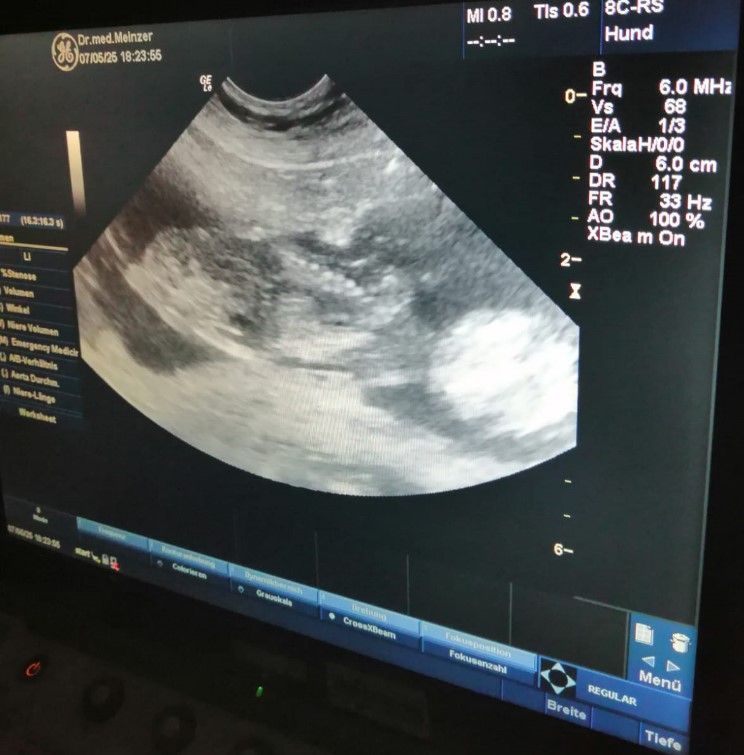

Heute, am 07.05.2025 waren wir bei unserer Tierärztin Sita Meinzer in Moosburg und haben ein Ultraschall machen lassen.

Es bestätigte sich, was wir schon gesehen haben, unsere Dior wird wieder Mama:-)).

Es sind einige Fleckenzwerge, die sich da auf den Weg machen.

Jetzt sind es noch gut 2 Wochen und die spannende Reise der Welpenaufzucht kann beginnen..